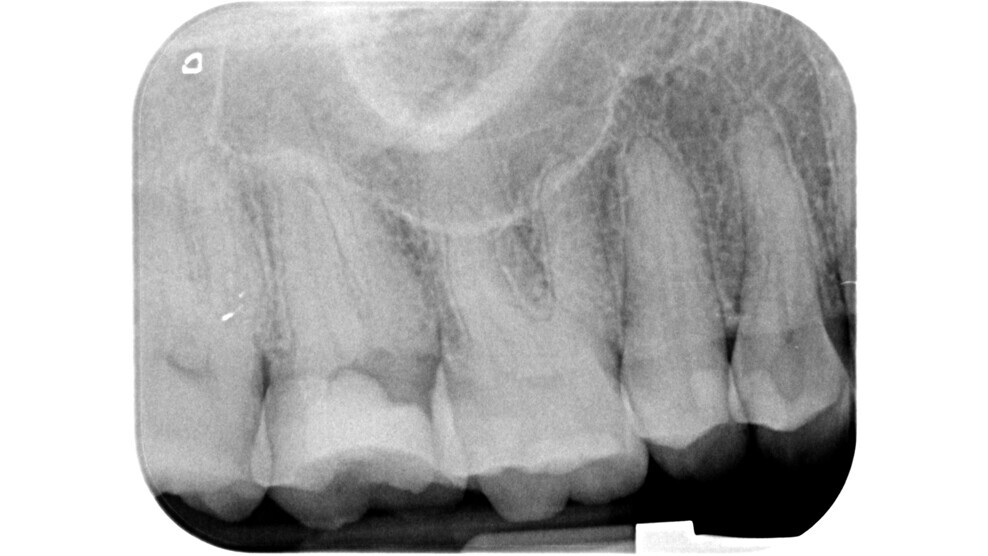

Fig. 6: Pre-op radiograph of a mesially tilted mandibular molar with irreversible pulpitis (probable colonisation from the distal periodontal lesion).

Fig. 7: Post-op radiograph showing the correct insertion axis during the preparation of the access cavity.

The current approach is towards a conservative access cavity that can guarantee enough visibility inside the pulp chamber to carry out shaping, irrigation and obturation, the pillars of endodontics. The first step to preparing an access cavity with these characteristics is the clinical and radiographic assessment of the tooth to be treated. The clinician should carefully evaluate the following important aspects that can yield valuable information for the approach to access cavity preparation: the position and inclination of the tooth (Figs. 6 & 7), the 3D extension of the carious process if present, the quality of pre-existing restorations and the relationship to the periodontium.